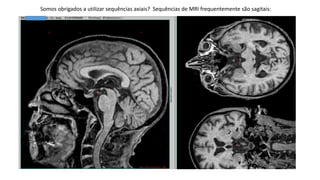

Somos obrigados a utilizar sequências axiais? Sequências de MRI frequentemente são sagitais:

Somos obrigados autilizar sequências axiais? Sequências de MRI frequentemente são sagitais: